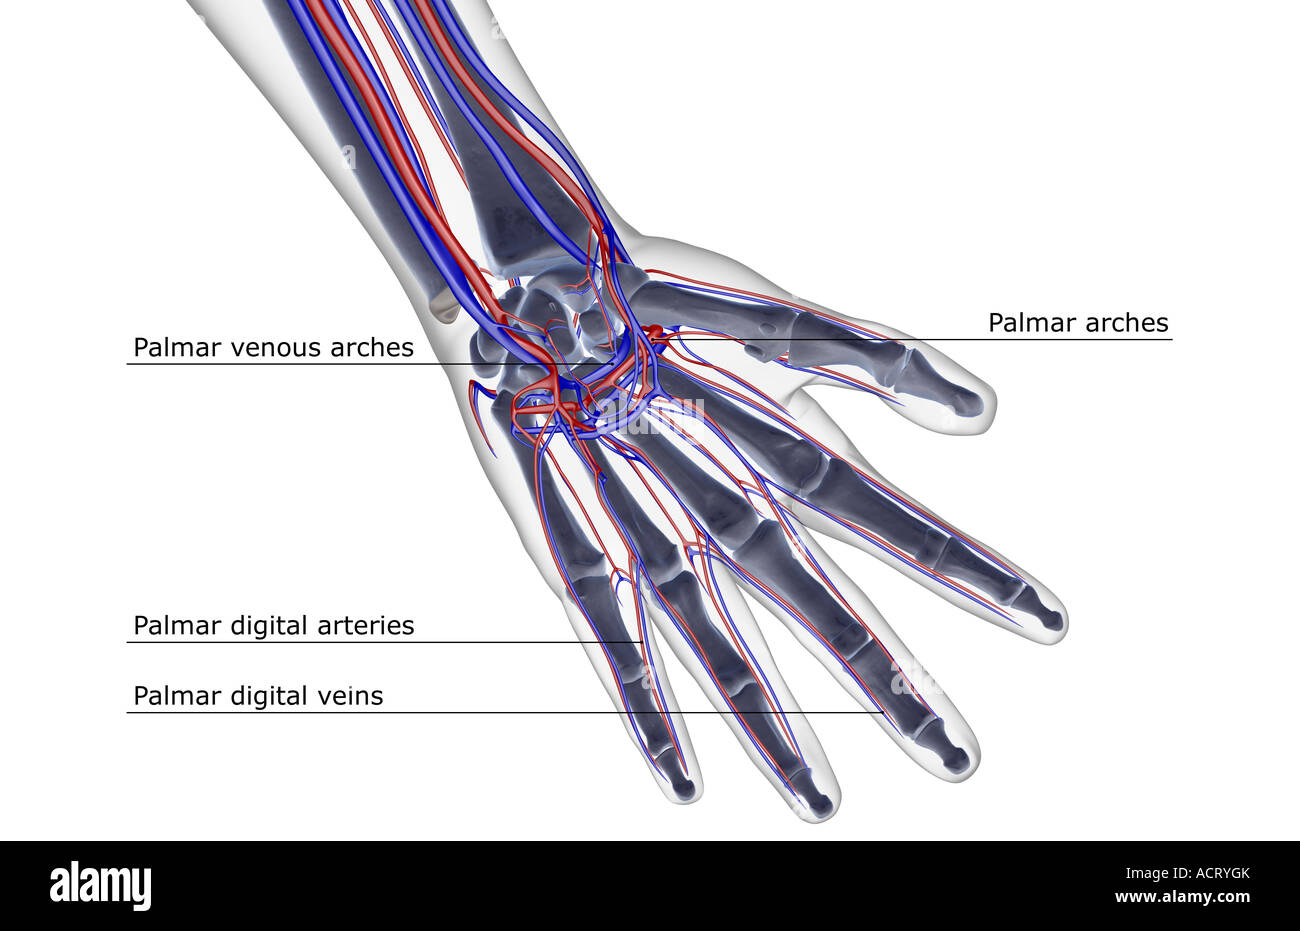

The blood supply of the hand Stock Photohttps://www.alamy.com/image-license-details/?v=1https://www.alamy.com/stock-photo-the-blood-supply-of-the-hand-13221234.html

The blood supply of the hand Stock Photohttps://www.alamy.com/image-license-details/?v=1https://www.alamy.com/stock-photo-the-blood-supply-of-the-hand-13221234.htmlRFACRYGK–The blood supply of the hand